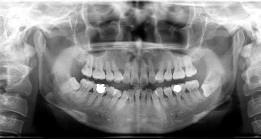

多项选择题引起智齿冠周炎的因素有 ( )

A、下颌第3磨牙阻生

B、下颌第3磨牙龋齿